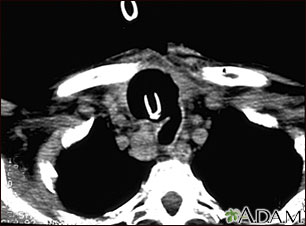

A chest CT (computed tomography) scan is an imaging method that uses x-rays to create cross-sectional pictures of the chest and upper abdomen.

A CT scan quickly creates detailed pictures of the body. The test may be used to get a better view of the structures inside the chest. A CT scan is one of the best ways of looking at soft tissues such as the heart and lungs.

A chest CT may show many disorders of the heart, lungs, mediastinum, or chest area, including: